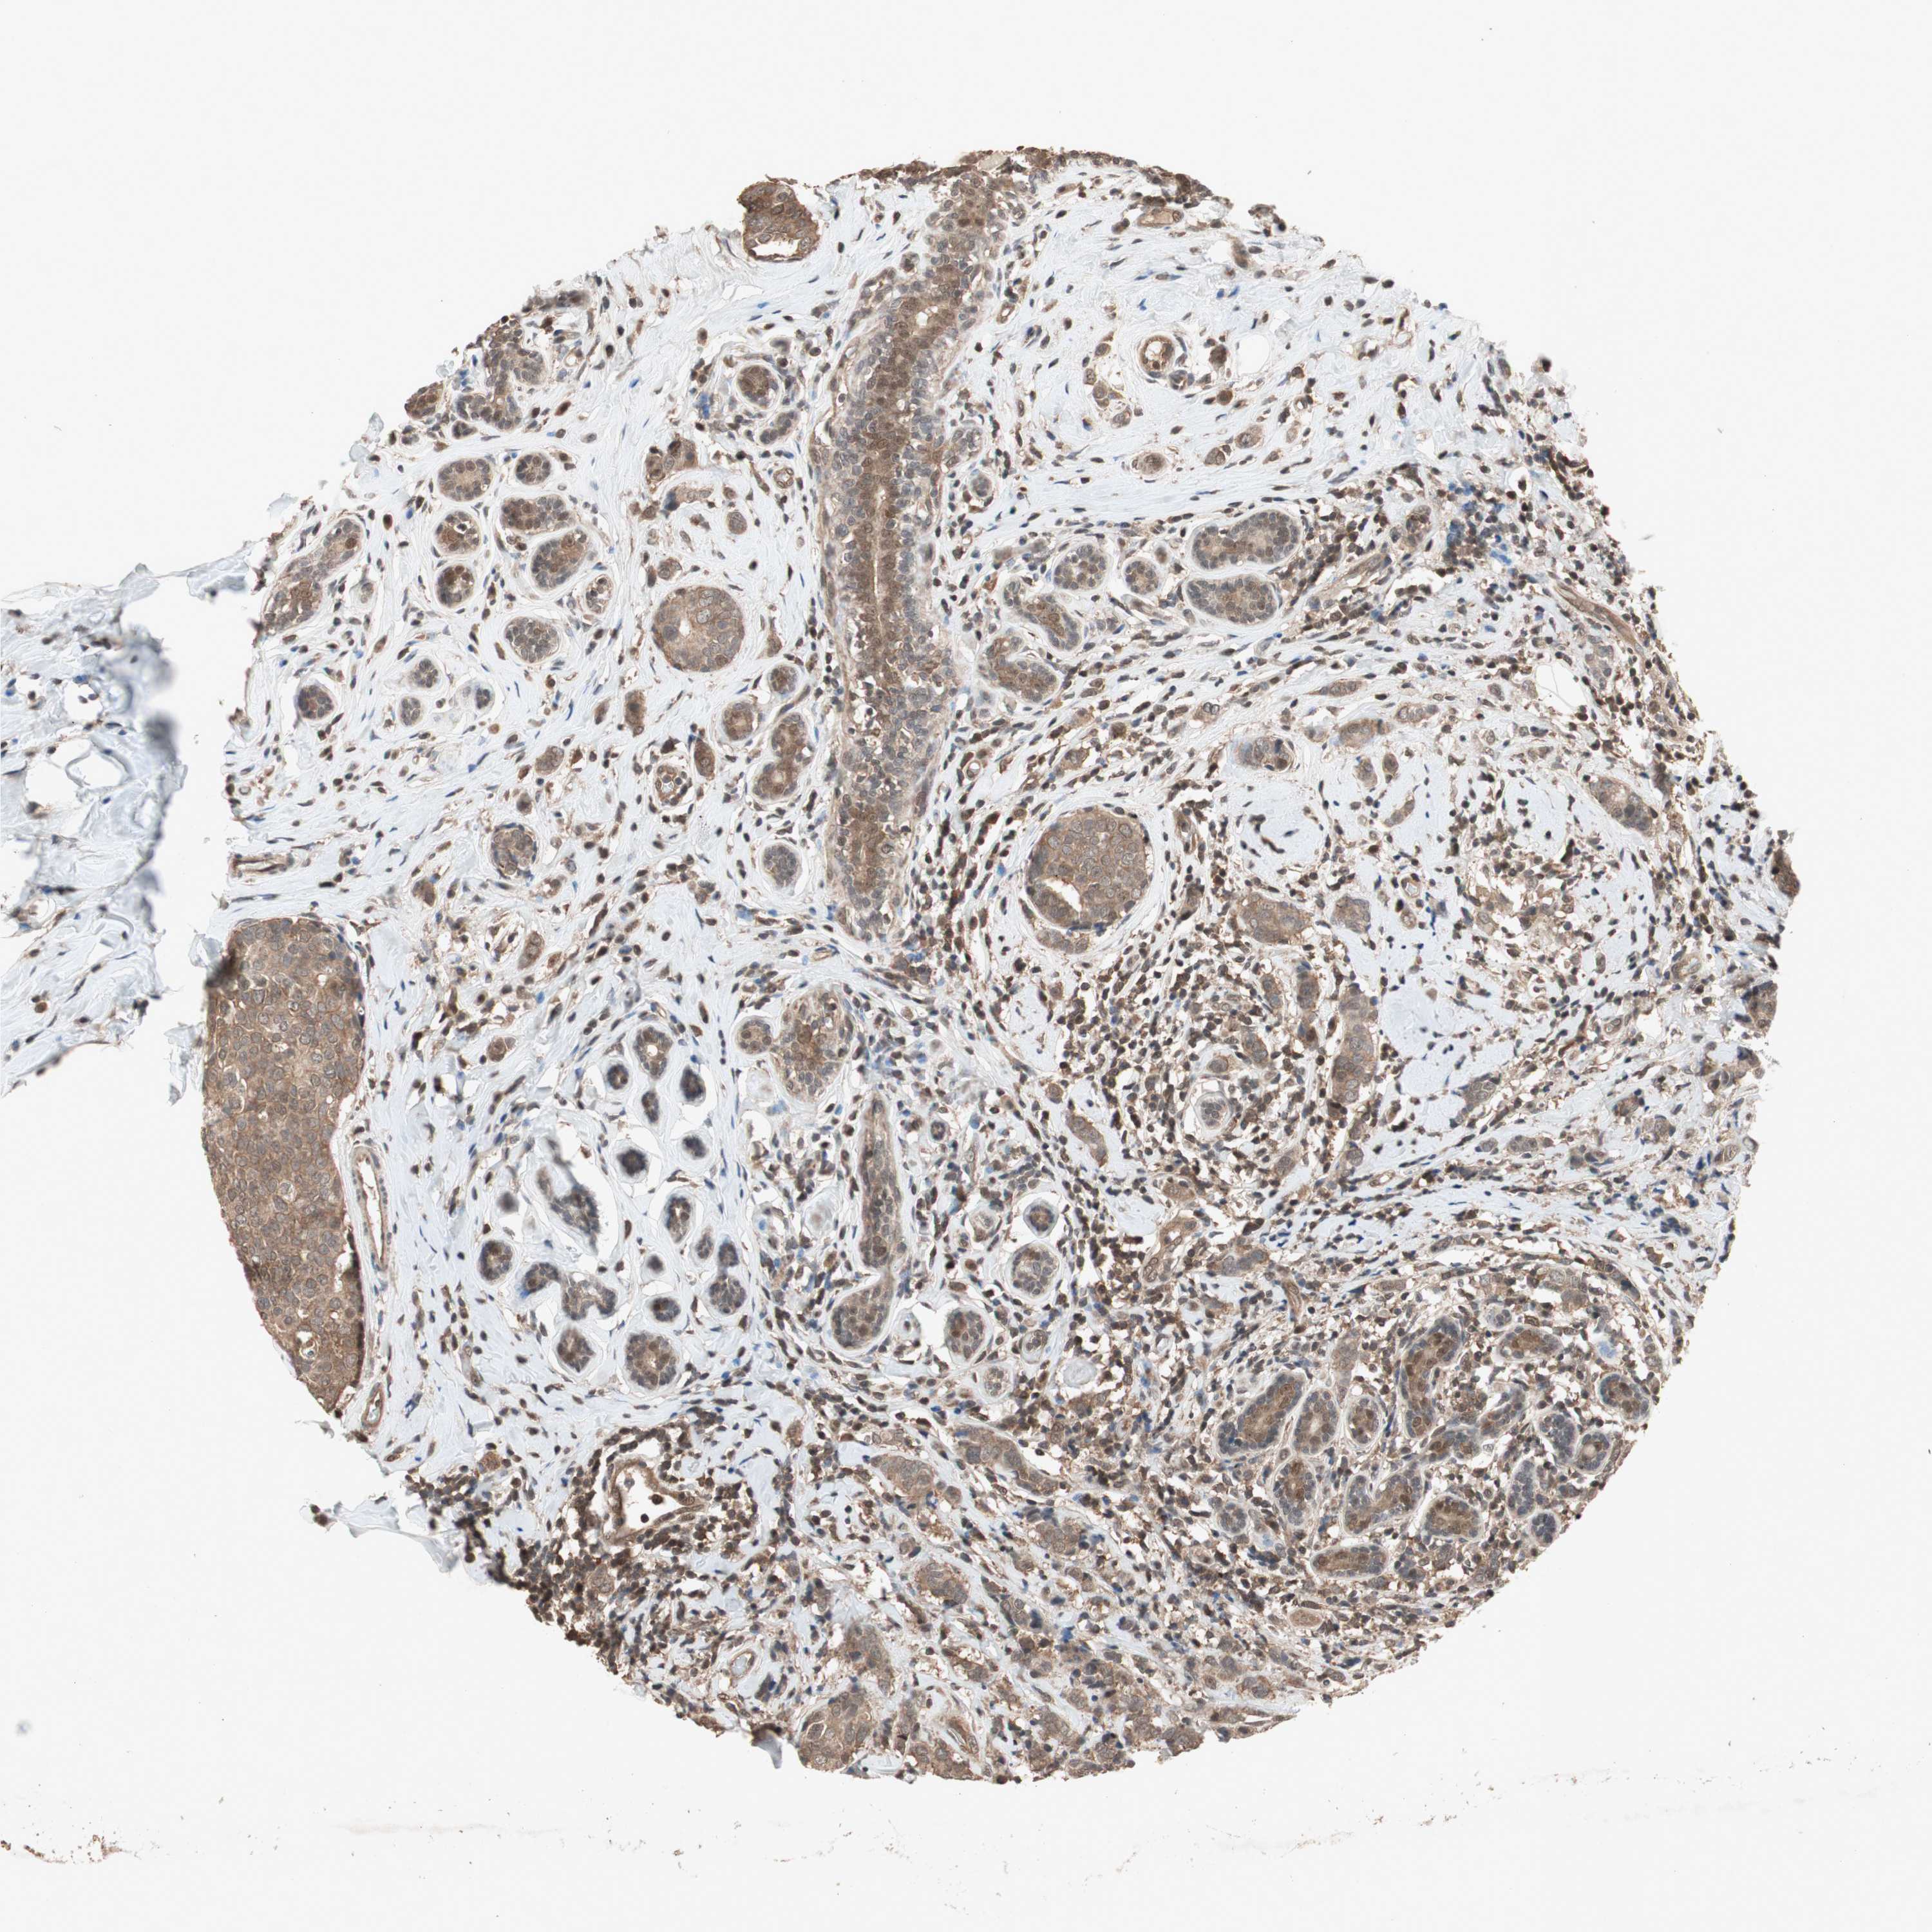

CANCER BREAST CANCER Show tissue menu

BRCA TCGA BRCA VALIDATION PROTEIN EXPRESSION

Breast cancer

Human cancer

Breast invasive carcinoma